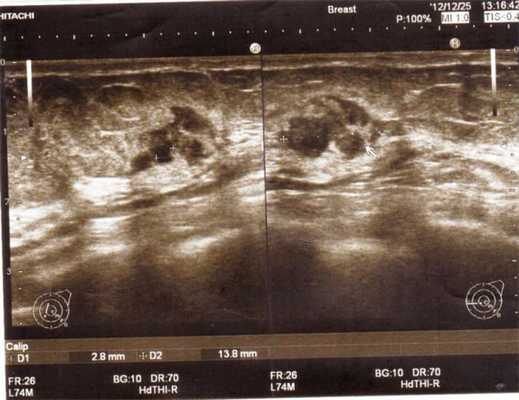

- Фиброаденома — разрастание фиброзной ткани с чёткими краями, вызванное гормональным сбоем. На экране монитора фиброаденома отображается объёмным новообразованием круглой, овальной или дольчатой формы. Эхогенность неоднородная, имеет заднее акустическое усиление. Контуры в некоторых случаях бывают ровными, но в большинстве случаях имеют неровные края и неоднородную гипоэхогенность.

- Отличить фиброаденому от рака позволяет дополнительное допплеровское исследование. При доброкачественном образовании кровотока практически нет, а единичные сосуды имеют низкие скоростные показатели кровоснабжения. Онкообразование хорошо снабжается кровью и имеет сетку сосудов и капилляров.